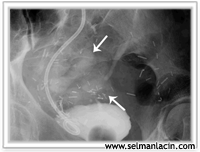

Rahim ağzı, rahimin hazneye (vajinaya) uzanan küçük bölümüdür. Bu bölümden çıkan kanserler erkenden bulgu verebilirler ve yıllık jinekolojik kontrollerle erkenden tanınabilirler.